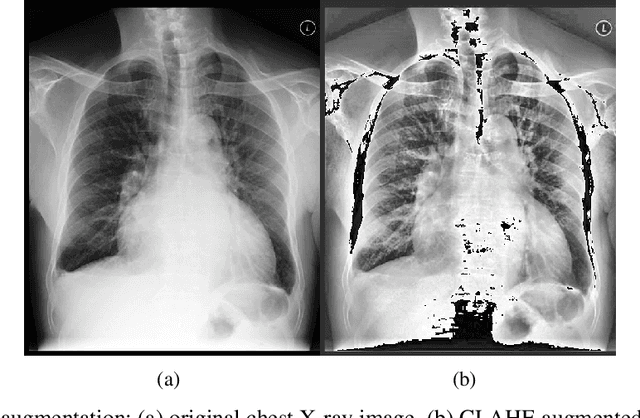

Abstract:With the increasing availability of diverse data types, particularly images and time series data from medical experiments, there is a growing demand for techniques designed to combine various modalities of data effectively. Our motivation comes from the important areas of predicting mortality and phenotyping where using different modalities of data could significantly improve our ability to predict. To tackle this challenge, we introduce a new method that uses two separate encoders, one for each type of data, allowing the model to understand complex patterns in both visual and time-based information. Apart from the technical challenges, our goal is to make the predictive model more robust in noisy conditions and perform better than current methods. We also deal with imbalanced datasets and use an uncertainty loss function, yielding improved results while simultaneously providing a principled means of modeling uncertainty. Additionally, we include attention mechanisms to fuse different modalities, allowing the model to focus on what's important for each task. We tested our approach using the comprehensive multimodal MIMIC dataset, combining MIMIC-IV and MIMIC-CXR datasets. Our experiments show that our method is effective in improving multimodal deep learning for clinical applications. The code will be made available online.